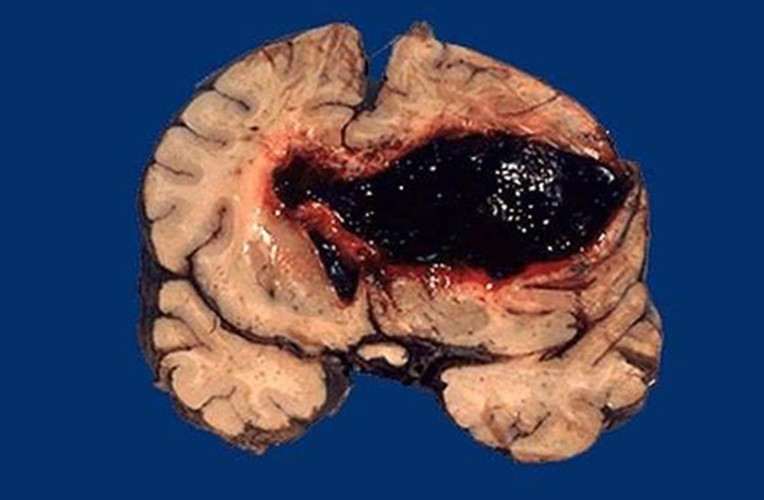

腦出血性梗死冠狀切片